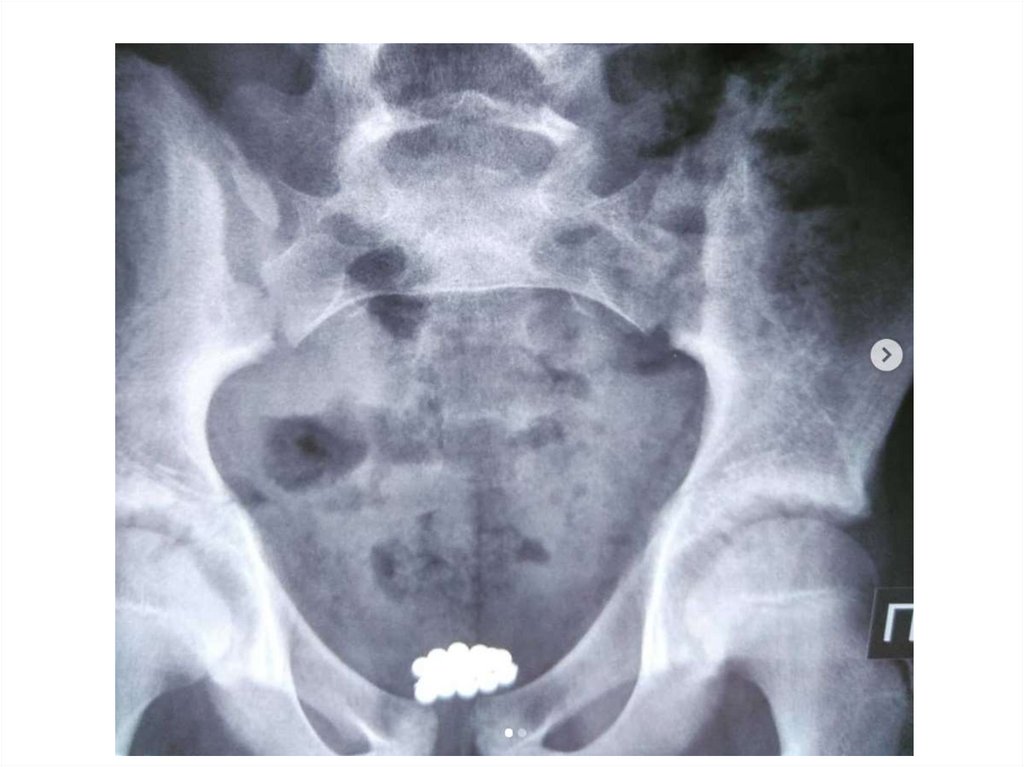

Обзорная рентгенограмма органов

брюшной полости

Рентгеноконтрастные

конкременты в

проекции правой

почки